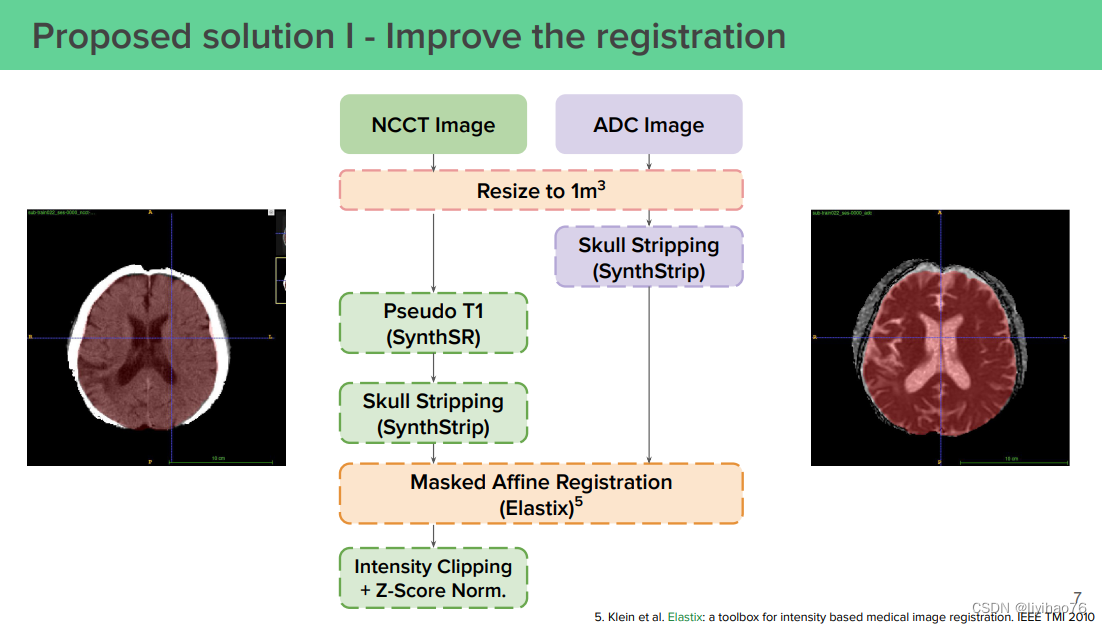

(0) 优化配准